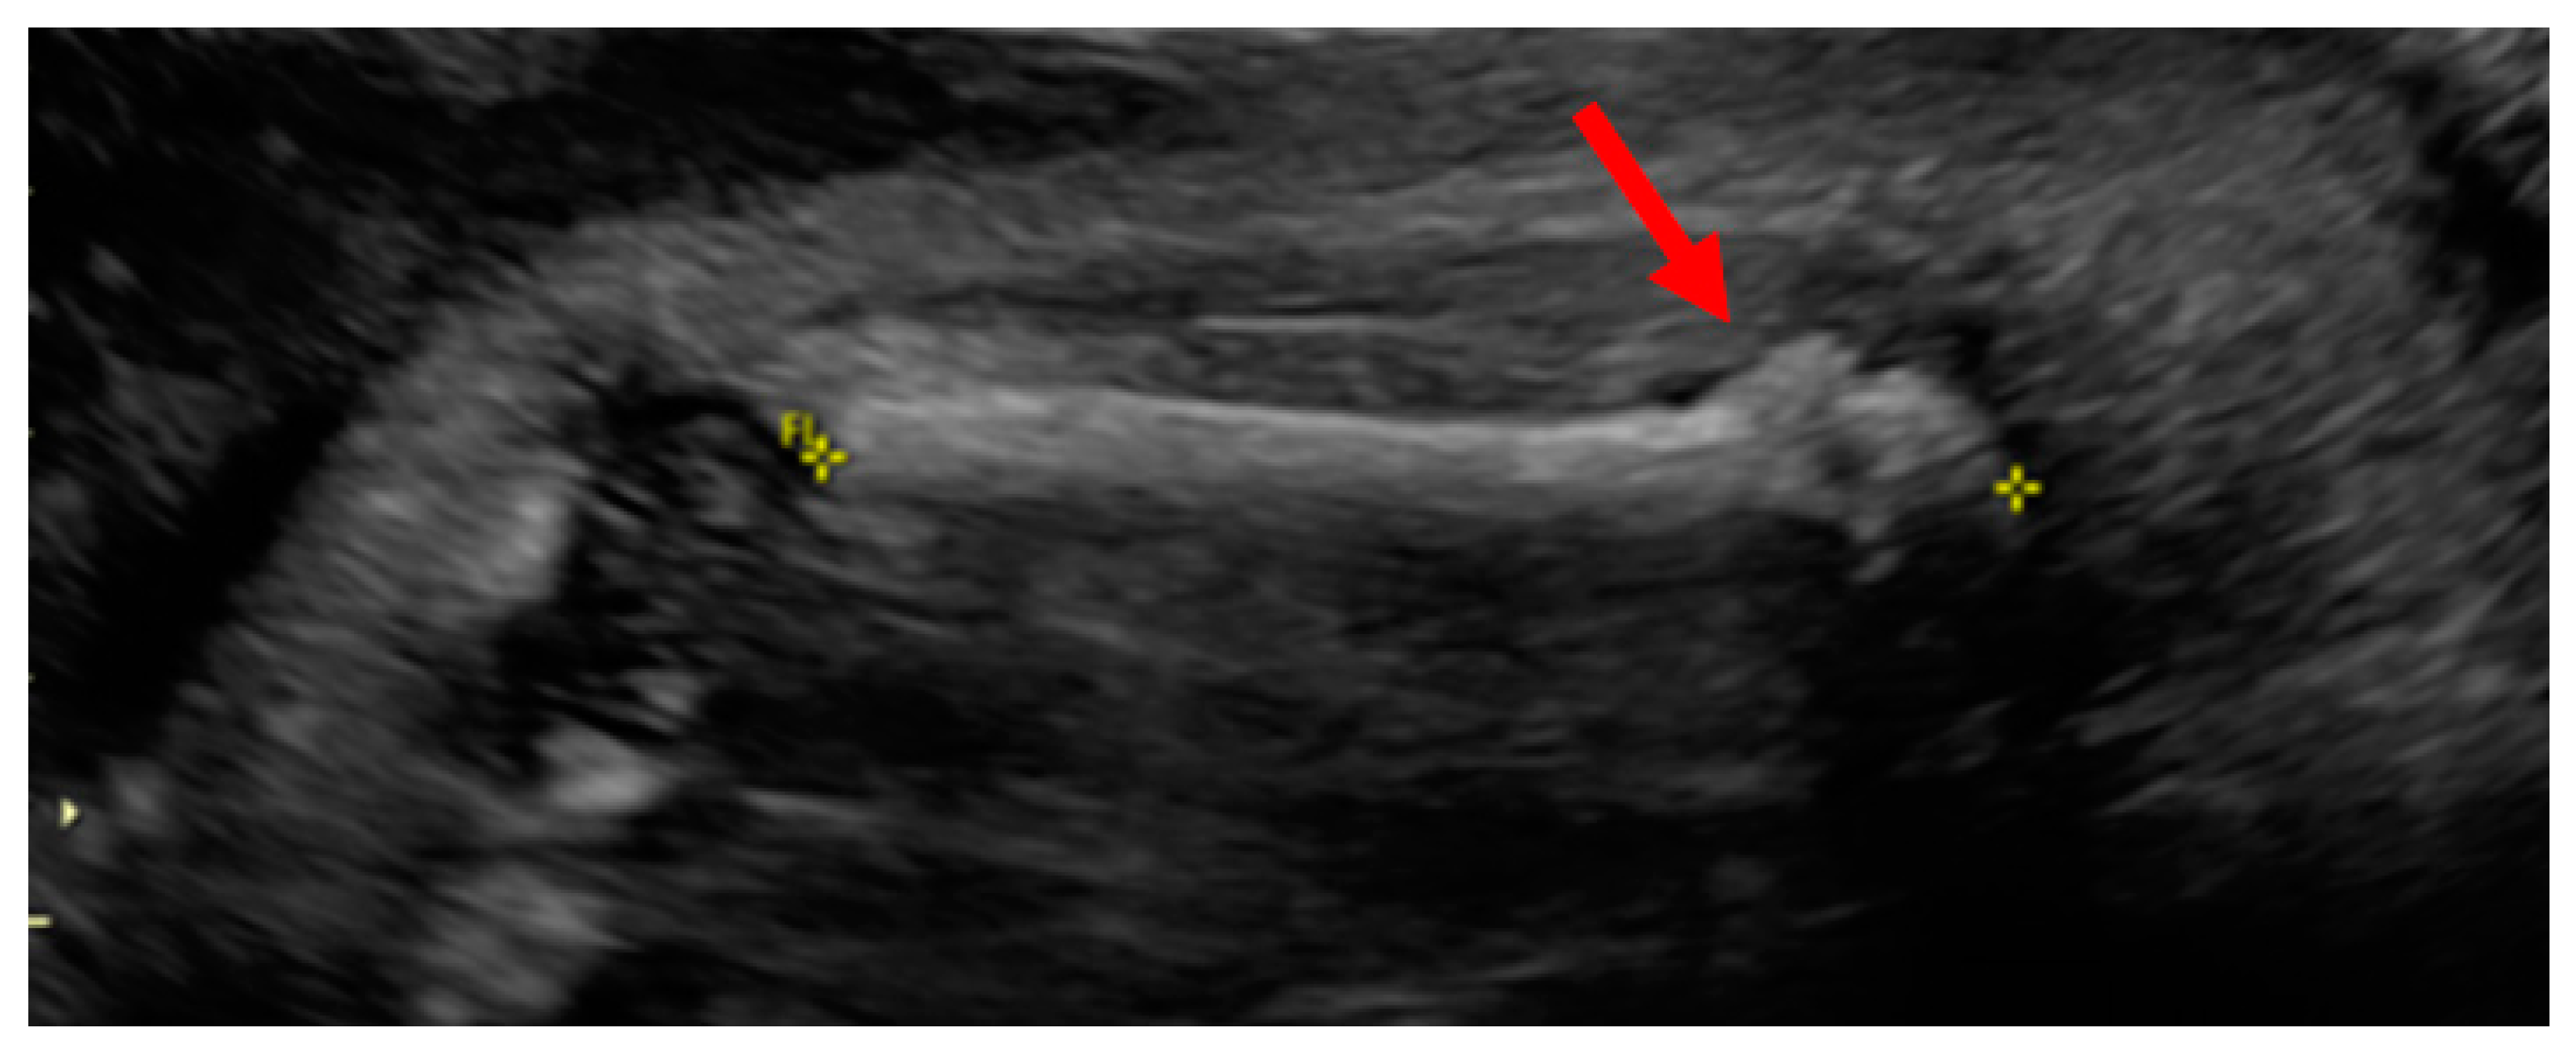

3.1. Phenotypes of the Patient and Parents